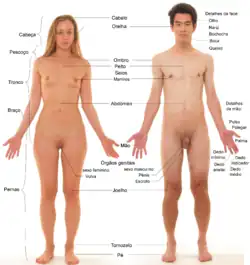

Anatomia humana

Os seres humanos são animais membros da ordem dos mamíferos, subfilo dos vertebrados e do filo dos cordados. À semelhança de todos os cordados, o corpo humano apresenta em determinado momento do desenvolvimento simetria bilateral, corda dorsal, fendas branquiais e e um tubo neural. Nos seres humanos, as duas primeiras características estão presentes apenas durante a fase embrionária. À medida que o embrião se desenvolve, a corda dorsal dá lugar à coluna vertebral característica dos vertebrados, as fendas branquiais desaparecem completamente e o tubo neural dá lugar à espinal medula.[26][27] À semelhança dos restantes mamíferos, o corpo humano apresenta como características proeminentes a presença de pelos, glândulas mamárias e sistema sensorial bastante desenvolvido. No entanto, apresenta também algumas diferenças significativas. É o único mamífero com postura bípede, o que modificou o plano corporal, e o cérebro é de longe o mais desenvolvido em todo o reino animal.[27]

O corpo humano adulto possui mais de 75 biliões de células. Cada célula é capaz de crescer, de metabolizar, de responder a estímulos e de se reproduzir, embora haja algumas exceções. Existem mais de 200 tipos diferentes de células no corpo humano que, em conjunto com a matriz extracelular, formam os quatro principais tipos de tecido: epitelial, muscular, nervoso e conjuntivo. Por sua vez, os tecidos formam órgãos individuais e cada órgão pode apresentar vários tipos de tecido. O tecido epitelial reveste a superfície do corpo, os órgãos internos, cavidades e passagens. Os tecidos musculares são contrácteis e constituem os músculos, enquanto que os tecidos nervosos constituem o sistema nervoso. O tecido conjuntivo liga as várias estruturas anatómicas entre si e é constituído por células bastante espaçadas.[27]

O corpo humano é constituído por nove sistemas orgânicos principais. O sistema tegumentar é constituído pela pele que reveste o corpo e as diversas estruturas a ela associadas, como os pelos, as unhas ou as glândulas sebáceas, e tem a função de proteger os outros órgãos. O sistema locomotor compreende os músculos esqueléticos e os ossos do esqueleto e tem função locomotora e de proteção dos órgãos internos. O sistema respiratório é constituído pelos pulmões, músculos da respiração e respetivas passagens e tem a função de extrair oxigénio do ar, fundamental para o metabolismo, devolvendo dióxido de carbono. O sistema circulatório ou cardiovascular é constituído pelo coração, vasos sanguíneos e sangue. O coração impulsiona a circulação do sangue, o qual tem a função de transportar oxigénio, nutrientes, células imunitárias, hormonas e resíduos entre as células das diversas partes do corpo. O sistema digestivo é constituído pela boca, esófago, estômago e intestinos e tem a função de processar os alimentos em nutrientes aproveitáveis pelo corpo, que são depois absorvidos pelo sangue ou pela linfa e os resíduos expulsos na forma de matéria fecal. O sistema excretor é constituído pelos rins, bexiga e respetivos canais e tem a função de remover os compostos de nitrogénio tóxicos da corrente sanguínea. O sistema endócrino é constituído pelos tecidos e glândulas que produzem hormonas, as quais atuam como uma rede de comunicações entre os vários sistemas. O sistema reprodutor, feminino ou masculino dependendo do sexo, é constituído pelos órgãos sexuais e permite a reprodução e a continuidade da espécie.[27]

Termos de localização

Os termos anatómicos usados para descrever a localização de determinada estrutura têm por base a posição anatómica de referência. Nos seres humanos, esta posição corresponde a uma pessoa de pé, com os pés ligeiramente afastados, braços esticados e as palmas das mãos abertas e viradas para a frente.[74] Quando os anatomistas mencionam o lado esquerdo ou o lado direito do corpo, referem-se à esquerda e direita do indivíduo, e não do observador. Ao observar um corpo na posição anatómica de referência, o lado esquerdo do corpo é o lado direito do observador e vice-versa. Os termos padronizados evitam confusão. Entre os termos mais usados estão:[75]:4

Regiões anatómicas

Os anatomistas dividem o corpo em regiões anatómicas. Na parte anterior do tronco situa-se o "tórax", na região superior, e o "abdómen" na região inferior. Na parte posterior do tronco, ou costas, situa-se o a "região dorsal", na parte superior, e a "região lombar" na parte inferior. A região das omoplatas é denominada região escapular e a região do esterno é denominada "região esternal". A região entre o peito e a pelve denomina-se "região abdominal". O peito pode é também denominado "região mamária", a axila como "região axilar" e o umbigo como "região umbilical". A pelve entre o abdómen e as coxas corresponde à "região hipogástrica". As virilhas, em que a coxa se une ao tronco, são a "região inguinal". Os glúteos correspondem à região glútea e a púbis à "região púbica".[74]

O braço completo é denominado "região braquial". A parte anterior do cotovelo é denominada "região cubital" e a parte posterior "região olecraniana". O antebraço corresponde à "região antebraquial". O punho e o carpo são denominados "região carpal". A palma da mão é denominada "região palmar". O dedo polegar é denominado "pólex" e os restantes dedos divididos em falanges proximais, médias e distais, nas extremidades. Os anatomistas dividem os membros inferiores em coxa (secção entre a anca e o joelho) e perna (secção entre o joelho e o tornozelo). A coxa e o fémur correspondem à "região femoral". A parte anterior do joelho, a rótula, corresponde à "região rotuliana" e a parte posterior, o poplíteo, à "região poplítea". A generalidade da perna é a "região crural"; a referência apenas à parte lateral denomina-se "região peroneal" e à parte posterior, os gémeos, a "região sural". O tornozelo e o tarso denominam-se "região tarsal" e o calcanhar a "região calcânea". O dedo grande do pé é referido como "hálux".[74]